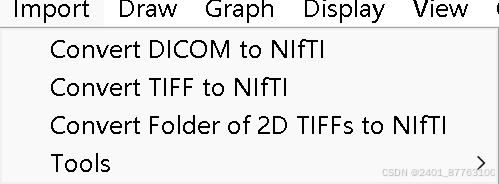

点击DICOM to NIFTI

把你想要转换的DICOM图像直接丢进去--记得在Output dirctory指定你转换后文件想要放到哪一个目录

第二步打开itk,勾画ROI----注意:你也可以不勾画ROI计算图像整体的SNR

把你刚刚转换的NII格式文件拖进去